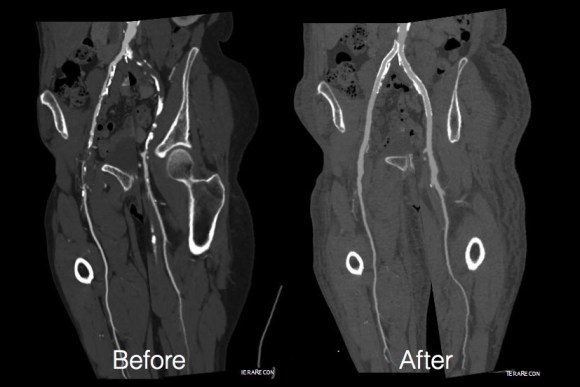

The remote endarterectomy of the external iliac artery remains patent. Compare this to the preop CTA which I found and wasn’t available when I posted this case originally:

The chronically occluded EIA can be readily seen. The artery shown in the current CTA is that recanalized artery.

CTA (pictured above and below) showed a 5.1cm infrarenal AAA with an hourglass shaped neck with moderate atherosclerosis in the neck, an occluded left common iliac artery with external iliac artery reconstitution via internal iliac artery collaterals, and a right external iliac artery occlusion with common femoral artery reconstitution. There was calcified right common femoral artery plaque.

The patient recovered well and was sent home several days postprocedure. He returned a month later with healed wounds and palpable peripheral pulses. He no longer had claudication and CTA showed the aneurysm sac to have no endoleak (figures below).